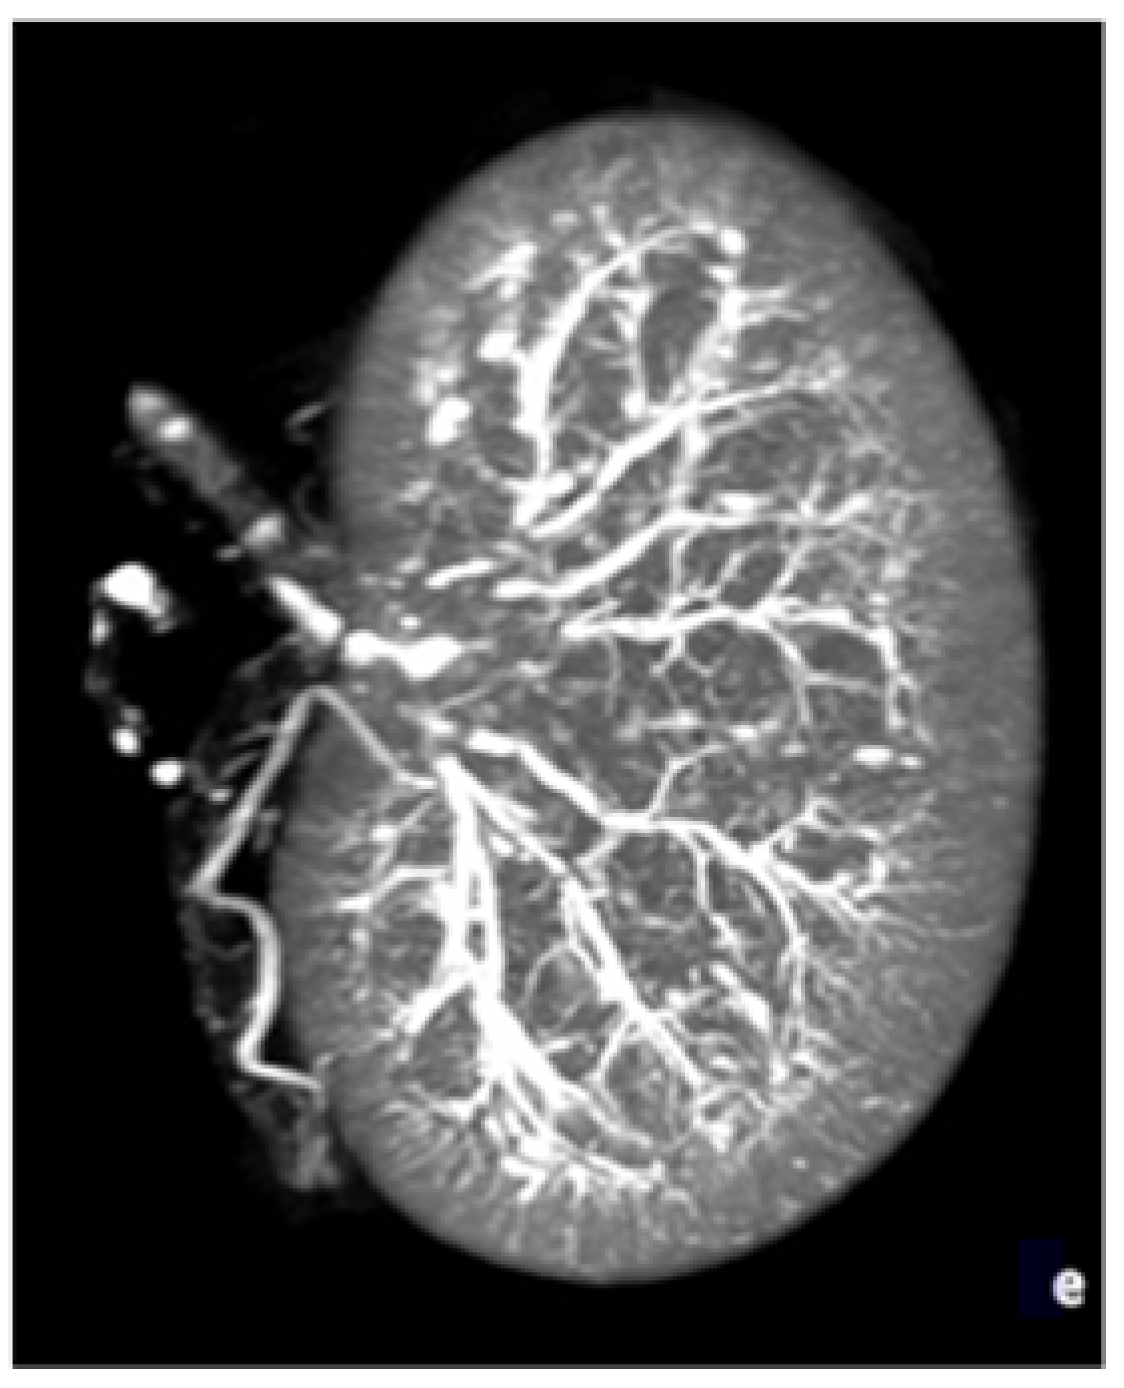

2.1. Experimental Model and Procedure

2.2. Acquisition and Reconstruction Parameters for Micro-CT

2.3. Data Analyses and Outcomes

2.3.1. Objective Outcomes

2.3.2. Subjective Outcomes

2.3.3. Image-Quality Criteria